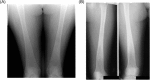

Gaucher disease (GD) is a rare, genetic lysosomal disorder leading to lipid accumulation and dysfunction in multiple organs. Involvement of the skeleton is one of the most prevalent aspects of GD and a major cause of pain, disability, and reduced quality of life. Uniform recommendations for contemporary evaluation and management are needed. To develop practical clinical recommendations, an international group of experienced physicians conducted a comprehensive review of 20 years' of the literature, defining terms according to pathophysiological understanding and pointing out best practice and unmet needs related to the skeletal features of this disorder. Abnormalities of bone modeling, reduced bone density, bone infarction, and plasma cell dyscrasias accompany the displacement of healthy adipocytes in adult marrow. Exposure to excess bioactive glycosphingolipids appears to affect hematopoiesis and the balance of osteoblast and osteoclast numbers and activity. Imbalance between bone formation and breakdown induces disordered trabecular and cortical bone modeling, cortical bone thinning, fragility fractures, and osteolytic lesions. Regular assessment of bone mineral density, marrow infiltration, the axial skeleton and searching for potential malignancy are recommended. MRI is valuable for monitoring skeletal involvement: It provides semiquantitative assessment of marrow infiltration and the degree of bone infarction. When MRI is not available, monitoring of painful acute bone crises and osteonecrosis by plain X-ray has limited value. In adult patients, we recommend DXA of the lumbar spine and left and right hips, with careful protocols designed to exclude focal disease; serial follow-up should be done using the same standardized instrument. Skeletal health may be improved by common measures, including adequate calcium and vitamin D and management of pain and orthopedic complications. Prompt initiation of specific therapy for GD is crucial to optimizing outcomes and preventing irreversible skeletal complications. Investing in safe, clinically useful, and better predictive methods for determining bone integrity and fracture risk remains a need. © 2019 The Authors. Journal of Bone and Mineral Research Published by Wiley Periodicals Inc.